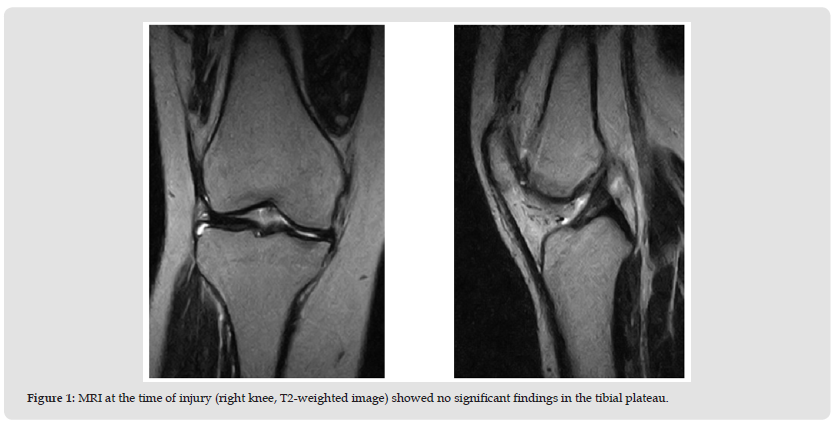

Due to persistent severe right knee pain and gait disturbance, a knee brace was applied, and conservative treatment, including muscle exercises, was initiated. One month later, follow-up MRI showed that the bone bruise had almost completely resolved (Figure 4), and her pain had gradually subsided; however she continued to experience episodes of knee instability. Arthroscopic examination revealed a slightly lax ACL and no meniscal tear. ACL augmentation was performed using a 7 mm single-bundle semitendinosus tendon graft (Figure 5). Postoperatively, a knee brace was worn on the right leg for 2 weeks, and range-motion exercises were allowed. Full weight bearing was allowed at 5 weeks. Six months after the surgery, the patient was largely aymptomatic and had resumed daily activities. Her Lysholm knee score was 82.